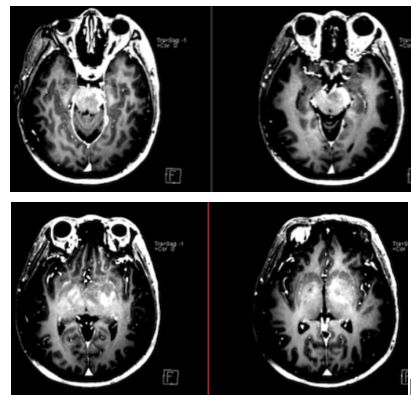

病例8(病例提供: 王浩玥 老师)

患者,女,43岁,因“头晕、行走不稳1月,加重伴左侧肢体无力10天”入院,1月前以“颅内感染、自身免疫性脑炎”收治。激素治疗效果欠佳。1月前增强:

此次复查平扫+强化:

答案:弥漫性大B细胞淋巴瘤

影像表现为:T2/FLAIR显示深部脑白质、皮层、基底节多灶性高信号。常见弥散受限,T2* GRE可见血液产物的“开花征”。T1WC C+多变,通常可见线样和斑片状强化,也可成环形、脑沟样等。脑膜和/或硬脑膜增强。有时类似于血管炎。